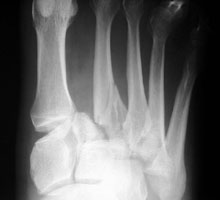

- Click on the image for a larger versionBAP and oblique radiographs of the foot. This is a different patient with a Lisfranc fracture-dislocation.